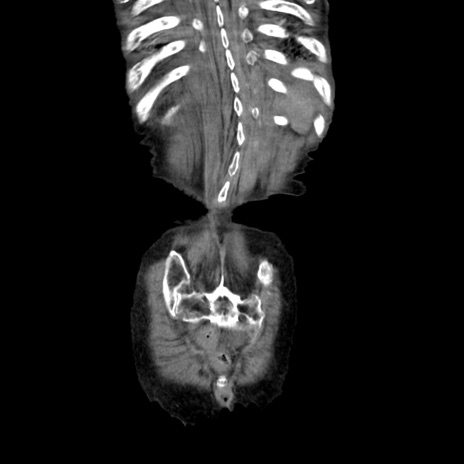

症例27(冠状断像)

【症例】80歳代女性

【主訴】嘔吐、腹痛

【現病歴】数時間前より嘔吐あり。心窩部痛出現し、徐々に右下腹痛あり。その後も数回嘔吐あり救急搬送となる。

【身体所見】腹部は膨隆しているが軟らかく圧痛なし。腸雑音はやや亢進。

【データ】WBC 12000、CRP 19.05